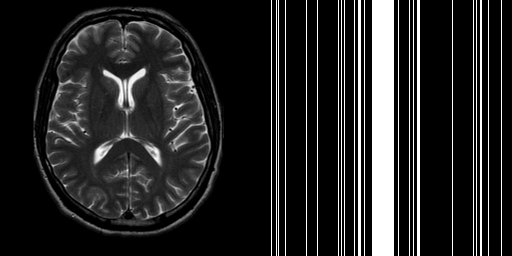

To test the performance of GADMM we choose a Shepp-Logan phantom of size and simulate the k-space data by taking the FFT of the phantom. Then we sample the k-space along 12 radial projections and reconstruct with Algorithm 1 and Algorithm 2. Parameter choices for Algorithm 1 were given in Subsection 3.1. In Algorithm 2 we set , and tune for optimal performance.

Fig. 3 compares reconstruction results for GADMM and Algorithm 1 after 300 iterations of each method. Algorithm 1 outperforms GADMM in SNR by more than 8dB and removes almost all the artifacts that GADMM fails to eliminate. SSIM and HFEN plots for these methods are presented in Fig. 4. The three variants of GADMM run for 121.2 (), 115.1 () and 110.2 () seconds while the Malitsky-Pock method runs for 119.6 seconds. We remark that numerical results of GADMM in this section were only provided to justify our unusual choice of Malitsky-Pock algorithm over ADMM-based methods which are more popular in constrained minimization settings. In the remainder of the paper we solely focus on Algorithm 1 and discard GADMM from further consideration.

We select a -sized -weighted axial brain scan from our collection along with a 20% Cartesian mask. In order to simulate upright and rotated image acquisition sequences, we consider two setups:

-

1.

The reference image is in upright orientation. The FFT of the image is taken, then the sampling mask is applied (see Fig. 5 (1)).

2.

The reference image is rotated from upright position, say, by (counterclockwise). The FFT is taken, then the sampling mask rotated by the same is applied (see Fig. 5 (2)).